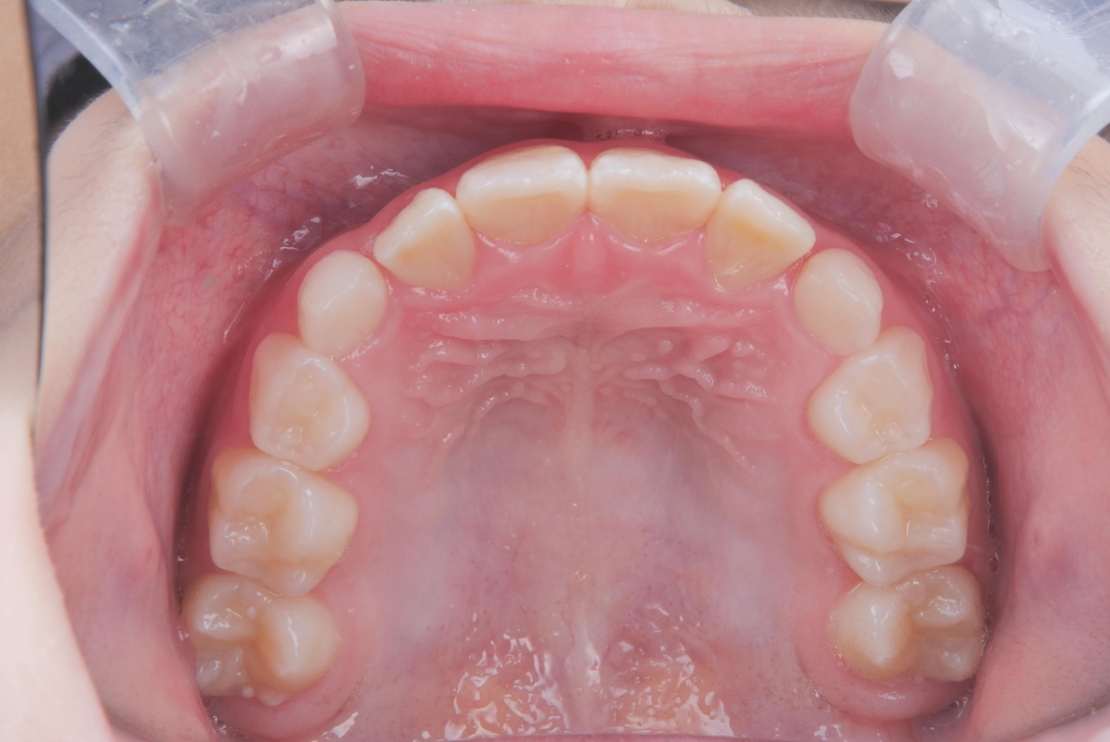

BEFORE

スタート時8歳の女の子の症例です。主訴は歯並びのガタつきでした。2年前に歯科医院で「顎が小さく、このままだと歯並びが悪くなる可能性がある」と指摘を受けていたことや、学校健診でチェックが入ったことをきっかけにご相談に来院されました。診査の結果、歯列のガタつきに加え、深い噛み合わせの状態も確認されました。

治療は、マウスピース矯正インビザライン・ファーストにて矯正治療を行い、成長を活かしながら歯列と噛み合わせを整えていきました。治療期間は1年2ヶ月で、ガタつきと深い噛み合わせが改善し、将来を見据えた安定した歯列環境を整えることができました。